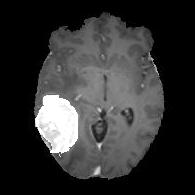

(a) Input image (b) DTAC Output (c) (d)